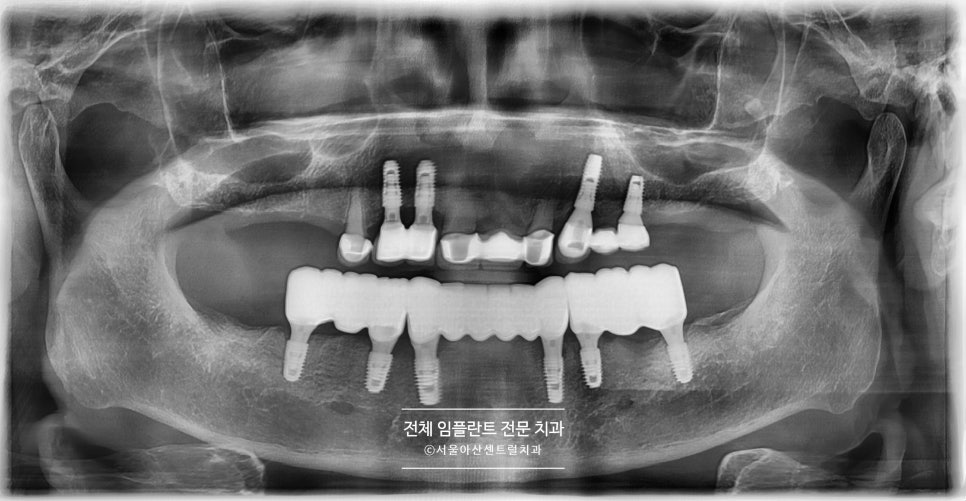

상기 환자분이 처음 성남치과에 내원하셨을때 사진을 보시면,

위(상악)에 치아들이 다수 치아우식증(충치)로 인해

많이 손상이 되어있는 상태였고

아래(하악)에 치아들은 수십년전

치아 13개를 한꺼번에 묶는 보철물이 되어있으나

마찬가지로 다수 치아우식증(충치)로 인해

많은 손상이 가해진 상태였습니다.

우선 위 파노라마 사진의 상태일 경우,

살릴 수있는 치아에는 브릿지 치료가 진행될 수 있습니다.

그 이후 발치가 필요한 치아는 모두 발치하고,

임플란트 식립이 필요하게 되는데요.